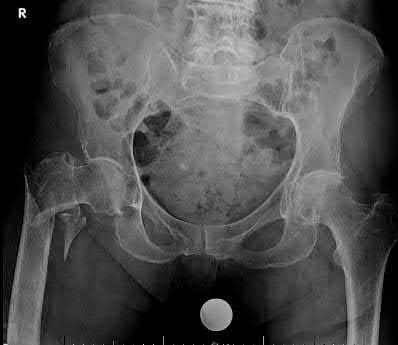

A 76-year-old male community ambulatory presented to clinic complaining of pain in the left groin that has been persistent for the last 8 months. Radiographs obtained from clinic are seen in Figure A. You suspect a femoral neck nonunion and obtain a CT scan which confirmed it. Which of the following statements is true?

A total hip arthroplasty (THA) after nonunion of a femoral neck fracture would provide the best long term outcomes in a 76-year-old male who is a community ambulator.

After nonunion of a femoral neck fracture, hemiarthroplasty and THA are good salvage option for the physiologically older patients. When deciding between these two options, THA is better for active and cognitively intact patients. THA is also indicated in patients with radiographic evidence of degenerative disease about the acetabulum. Hemiarthroplasty is advocated for patients who are older and less active.

Yang et al. retrospectively investigated the risk factors for nonunion in patients treated with cannulated screws. They reviewed 202 patients who had femoral neck fractures and were treated with internal fixation with cannulated screws. They identified that triangle configuration, displaced fracture, borderline or unacceptable reduction, and increased screw shaft subchondral purchase over the femoral neck were all risk factors for nonunion after internal fixation.

Inverted triangle configuration was found to increase rate of union.

Archibeck et al. retrospectively reviewed the outcomes of 102 THAs after failed internal fixation for a hip fracture (including both femoral neck and intertrochanteric). They concluded that the conversion of failed hip internal fixation has elevated risks compared to a primary THA, however, it may still be successful. The biggest concern for these patients postoperatively are periprosthetic fracture and dislocation.

Figures and Illustrations:

Figure A is an AP pelvic radiograph demonstrating a nonunion of a femoral neck fracture after suboptimal fixation with 3 cannulated screws in a triangle configuration.

Illustration A is an AP radiograph of the left hip in this patient following conversion to THA.

Illustration B is a radiograph demonstrating a valgus osteotomy. Illustration C shows an example of a femoral neck nonunion with varus malreduction.

Incorrect Answers:

Answer 2: Varus reduction is closely correlated with failure in this fixation method.

Answer 3: The patient's best outcome would be with THA.

Answer 4: This would be a good option in a younger patient, but given age and functional capacity, the best option is THA.

Answer 5: Patients with hemiarthroplasty have lower rates of dislocation.